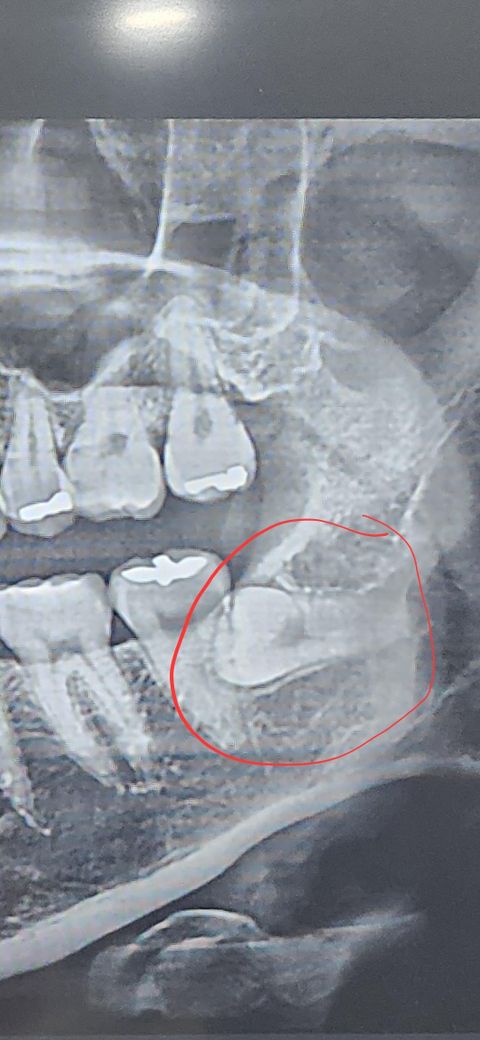

왼쪽 아래사랑니를 뽑았는데 통증이 지속되네요

지난주 금요일날 사랑니를 뽑았는데 아직도 너무 아프네요 이에서 쉰내도 나고 저리는데

이 이를 뽑았는데 그렇게 난이도가 있는 이인가요?

난이도는 상당히 높은 치아입니다. 통증은 2주 정도는 지속될 수 있으며 더 복용도 됩니다.

저정도 매복사랑니라면 잇몸도 크게 절개를 햇고 뼈삭제도 많이 햇을것같습니다. 2주 정도는 일단 지켜보셔야될것같습니다.